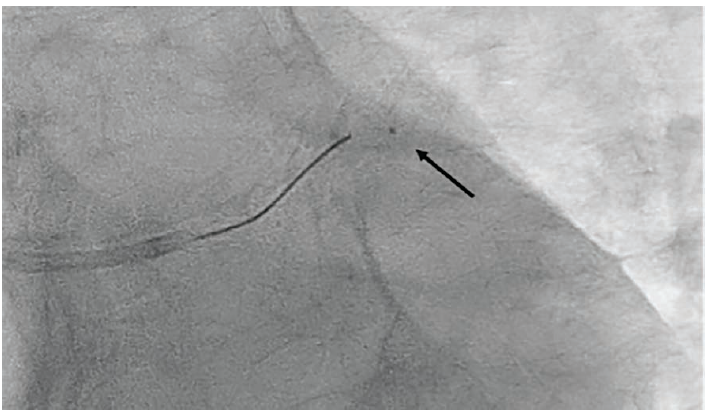

The LCx proximal lesion was the identifiable culprit for the NSTEMI presentation and we proceeded with PCI. The patient was pre-loaded with 600 mg of clopidogrel bisulfate. Due to the acute, near 90-degree take-off of the LCx and tortuosity in the right subclavian artery, we switched to a 6 Fr, 75 cm length R2P Destination Slender® Guiding Sheath. The LMCA ostium was engaged with a 6 Fr Extra Backup (EBU) 3.5 guide catheter (Medtronic) for the intervention. We used a 2.5 Fr, 130 cm length FineCross M3 coronary micro-guide catheter telescoped over a Runthrough® coronary guidewire. The FineCross M3 coronary micro-guide catheter supported the traversal of the unfavorable LCx angle, allowing us to advance the guidewire across the lesion into the distal LCx with minimal difficulty. The tip of the FineCross M3 catheter is highly radiopaque, enabling excellent visualization as seen in Figure 2, where the tip is at the acute angle. The Runthrough® guidewire was then exchanged for a Hi-Torque Wiggle™ Guidewire (Abbott) over the FineCross M3 microcatheter, using a Trapper Exchange Device (Boston Scientific) to facilitate removal of the microcatheter without losing wire position.